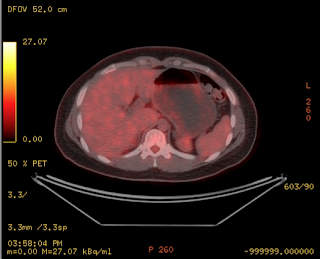

Cuadro clínico de 1 mes de evolución caracterizado por distensión abdominal e hiporexia.